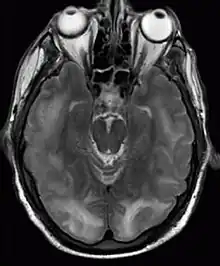

Posterior reversible encephalopathy syndrome visible on magnetic resonance imaging as multiple cortico-subcortical areas of T2-weighted hyperintense (white) signal involving the occipital and parietal lobes bilaterally and pons. | |

The diagnosis is typically made with magnetic resonance imaging of the brain. The findings most characteristic for PRES are symmetrical hyperintensities on T2-weighed imaging in the parietal and occipital lobes; this pattern is present in more than half of all cases.[1][3] FLAIR sequences can be better at showing these abnormalities.[4] Some specific other rare patterns have been described: the superior frontal sulcus (SFS) watershed pattern, a watershed pattern involving the entire hemisphere (holohemispheric), and a central pattern with vasogenic oedema in the deep white matter, basal ganglia, thalami, brainstem and pons.[1][3] These distinct patterns do not generally correlate with the nature of the symptoms or their severity, although severe edema may suggest a poorer prognosis.[1] If the appearances are not typical, other causes for the symptoms and the imaging abnormalities need to considered before PRES can be diagnosed conclusively.[4] In many cases there is evidence of constriction of the blood vessels (if angiography is performed), suggesting a possible overlap with reversible cerebral vasoconstriction syndrome (RCVS). Diffusion MRI may be used to identify areas of cytotoxic edema caused by poor blood flow (ischemia) but it is not clear if this prognostically relevant.[1][4] Abnormal apparent diffusion coefficient is seen in about 20% of cases.[4]